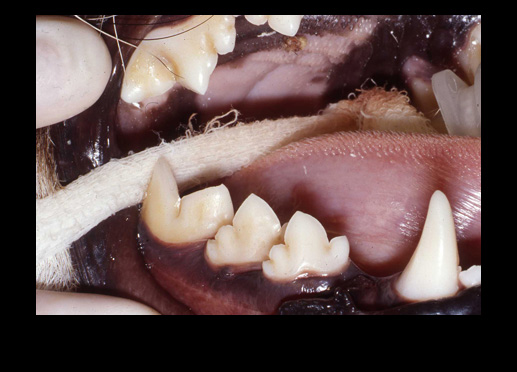

The WEDGE® is a one-piece, radiolucent mouth prop. The patented, anatomic design holds the carnivore mouth open during anesthesia by securely engaging the premolars and molars.

"The (Scheels) Veterinary mouth prop's biggest asset is its simplicity - open the mouth and stick it in!...it does not interfere with radiographic detail, can be ultrasounded, and autoclaved...can be used for dental and oral surgery procedures...is positioned within the mouth, unlike the spring loaded (extra-oral) devices which can be in the way of the operator and interfere with positioning the patient..."